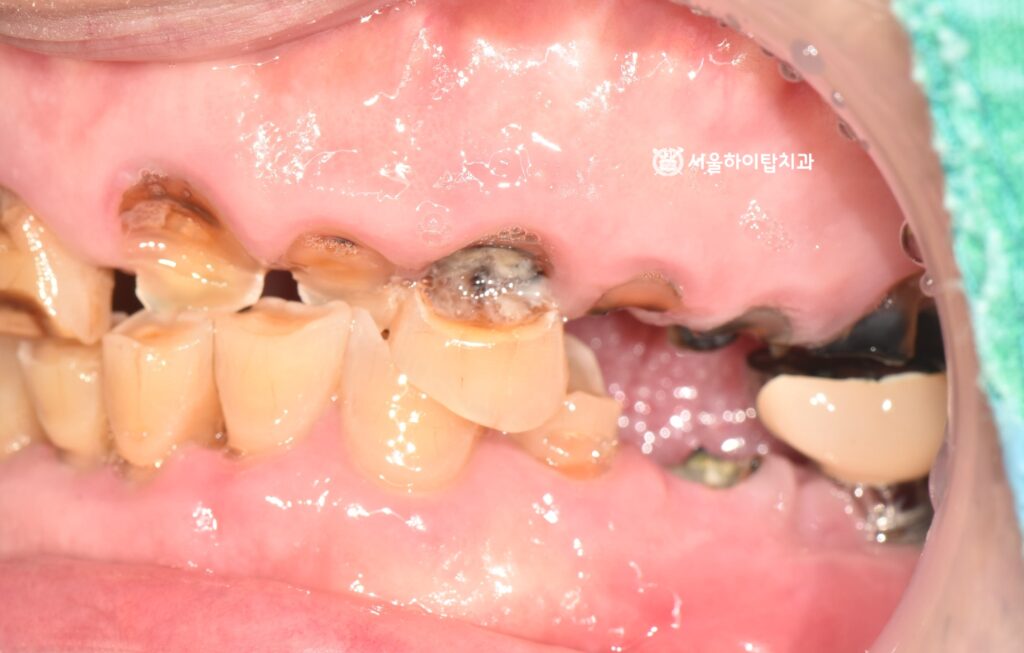

구강 내 모습을 확인하면,

전반적으로 치아와 잇몸 상태가 매우 좋지 않은 것을 알 수 있습니다.

치아는 이미 다수 파절되거나 상실된 상태였으며,

잇몸 또한 전반적으로 붓고 퇴축이 진행된 모습입니다.